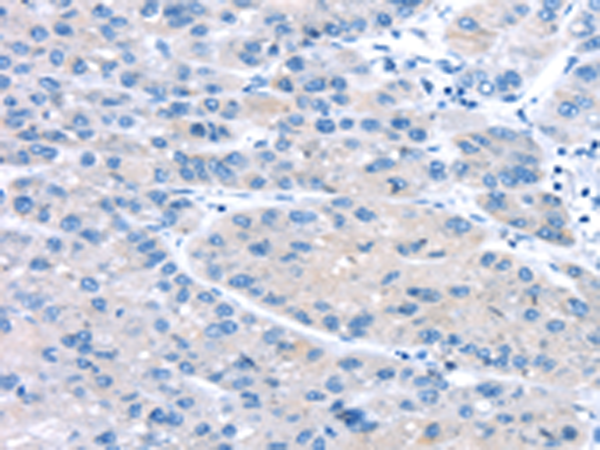

IHC positive control: |

Human liver cancer |

IHC Recommend dilution: |

10-50 |